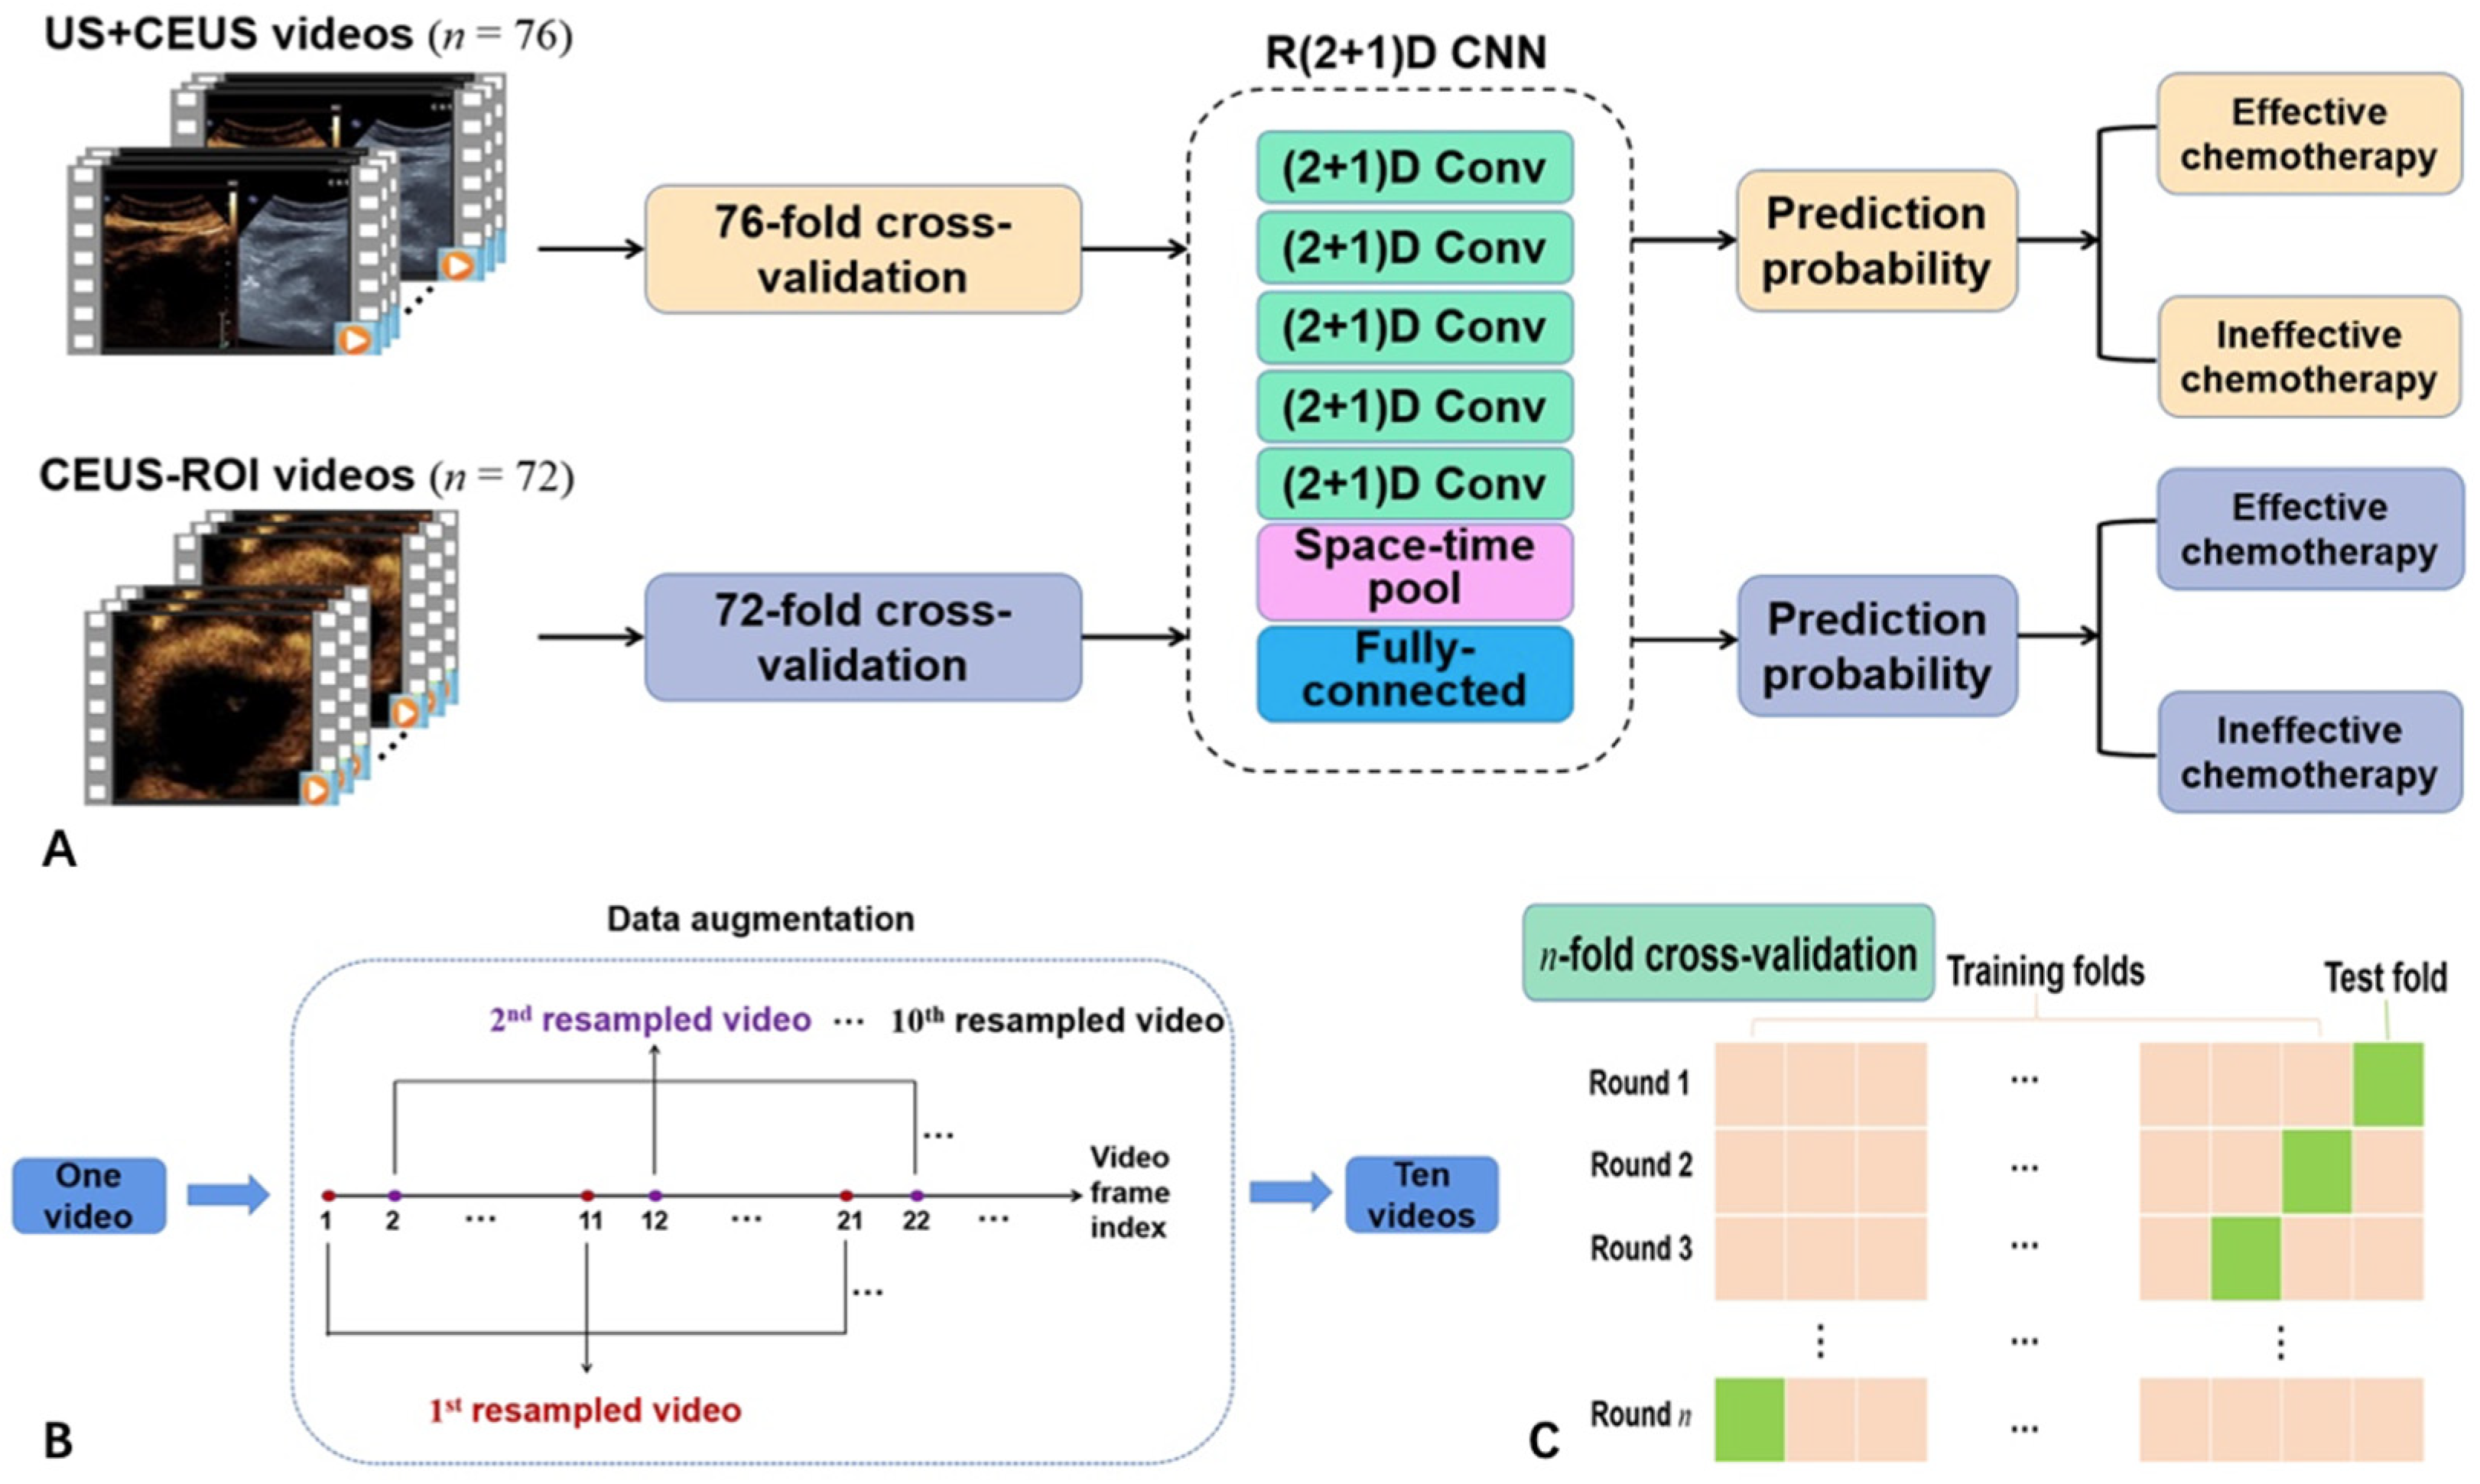

2.4. Network Structure

2.5. Experimental Configuration